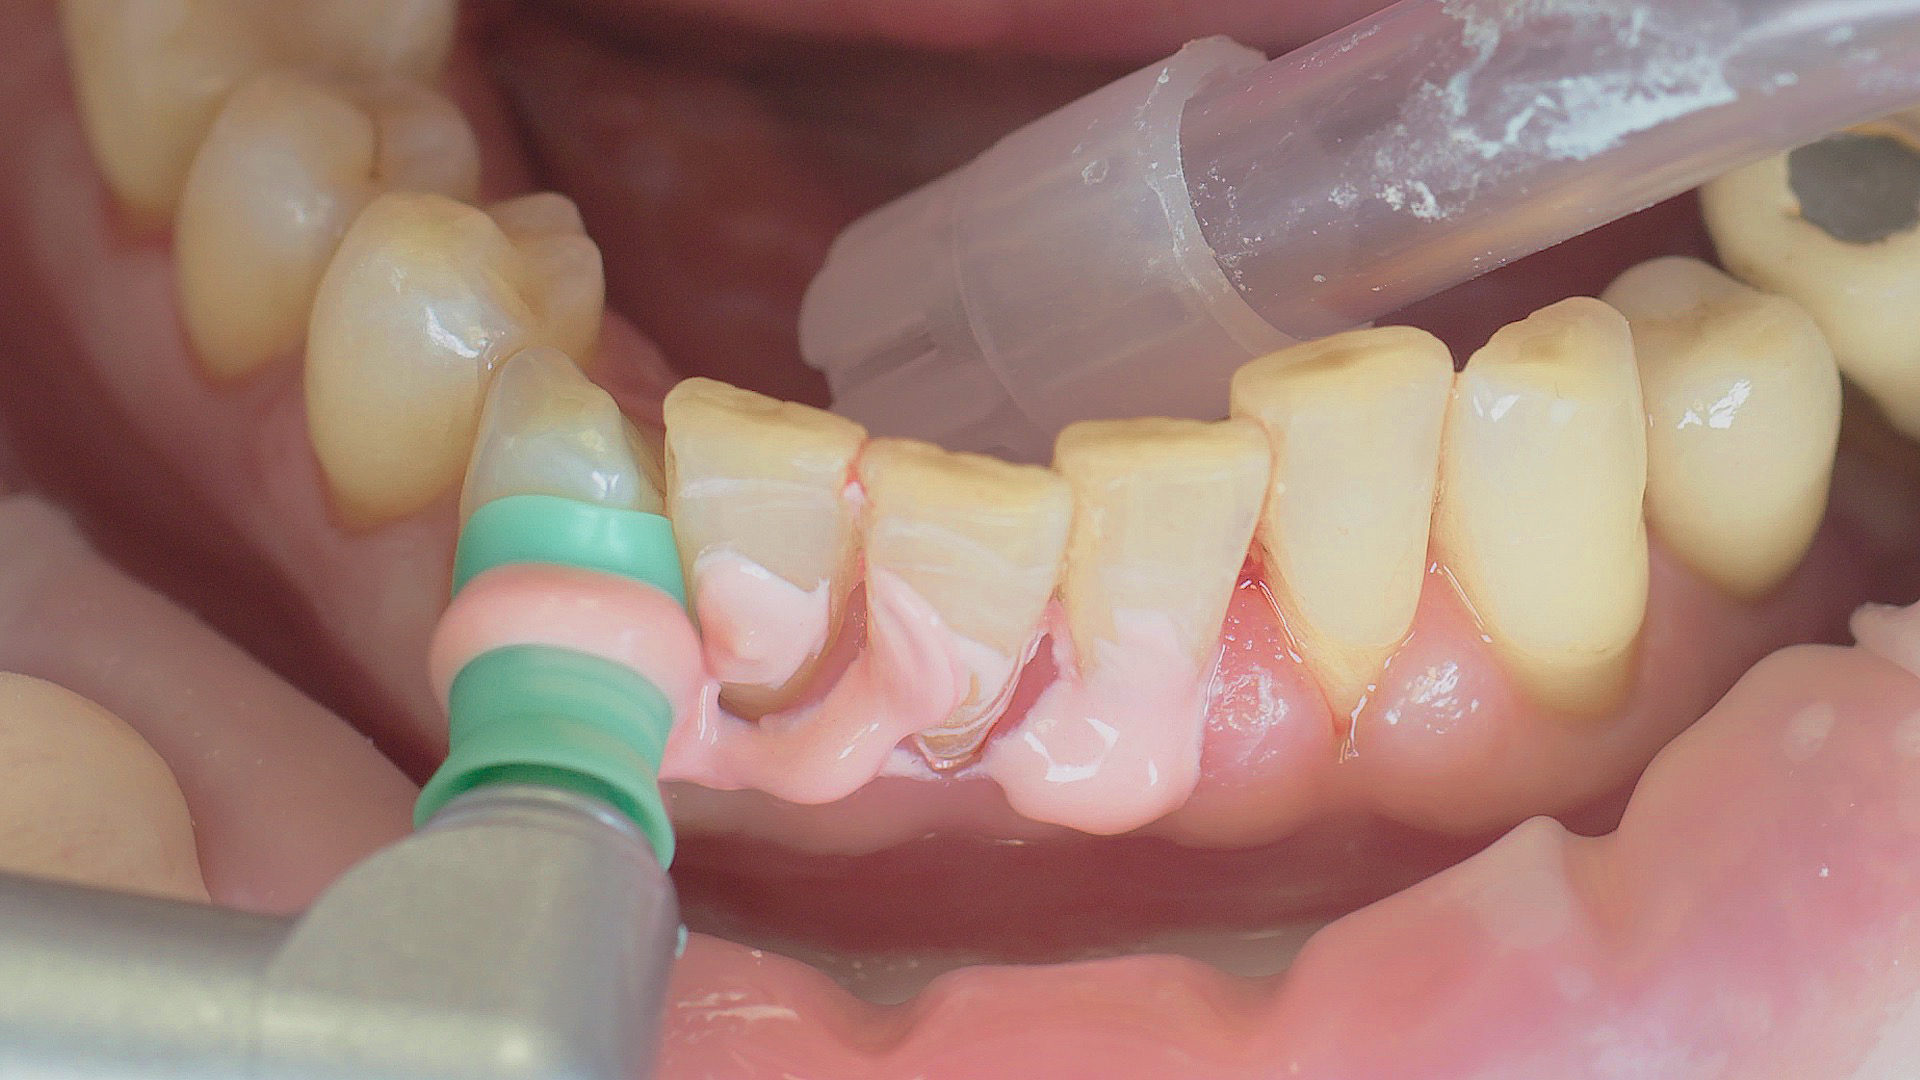

In the periodontal aftercare subsequent to implantation, soft (biofilm) and hard coatings are regularly professionally and mechanically removed.[16, 17] In the subgingival and supragingival areas, ultrasonic devices are generally used for this (Fig. 4), in combination with manual instruments where necessary. Alternatively, subgingival air polishing can be used in combination with periodontal attachments and powders.[18]

Removal of subgingival coatings (debridement) is carried out using sonic or ultrasonic devices and special periodontal tips as initial periodontal treatment (Fig. 3). Manual instruments can also be used. Further surgical and/or regenerative measures may be necessary, depending on the situation.